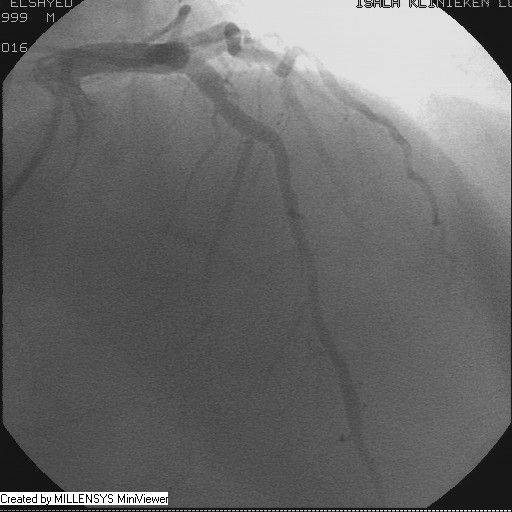

Patient transfered to Cardiac Catheterization Laboratory, coronary angiography showed atherosclerotic coronaries but without significant lesions, especially LAD that was patent with TIMI 3 flow (Figure 1- 5). Re-evaluation of the Angiography showed a small stump that can be for an occluded 1st diagonal (Figure 2a), at that level the LAD has a non-significant lesion.

Figure 5